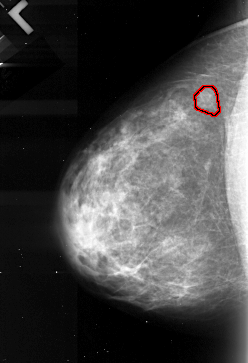

A_1103_1.LEFT_CC

LEFT_CC LINES 4351 PIXELS_PER_LINE 2971 BITS_PER_PIXEL 16 RESOLUTION 42 OVERLAY

FILE: A_1103_1.LEFT_CC.OVERLAY

TOTAL_ABNORMALITIES 1

ABNORMALITY 1

LESION_TYPE MASS SHAPE LOBULATED MARGINS MICROLOBULATED

ASSESSMENT 4

SUBTLETY 4

PATHOLOGY MALIGNANT

TOTAL_OUTLINES 1

BOUNDARY